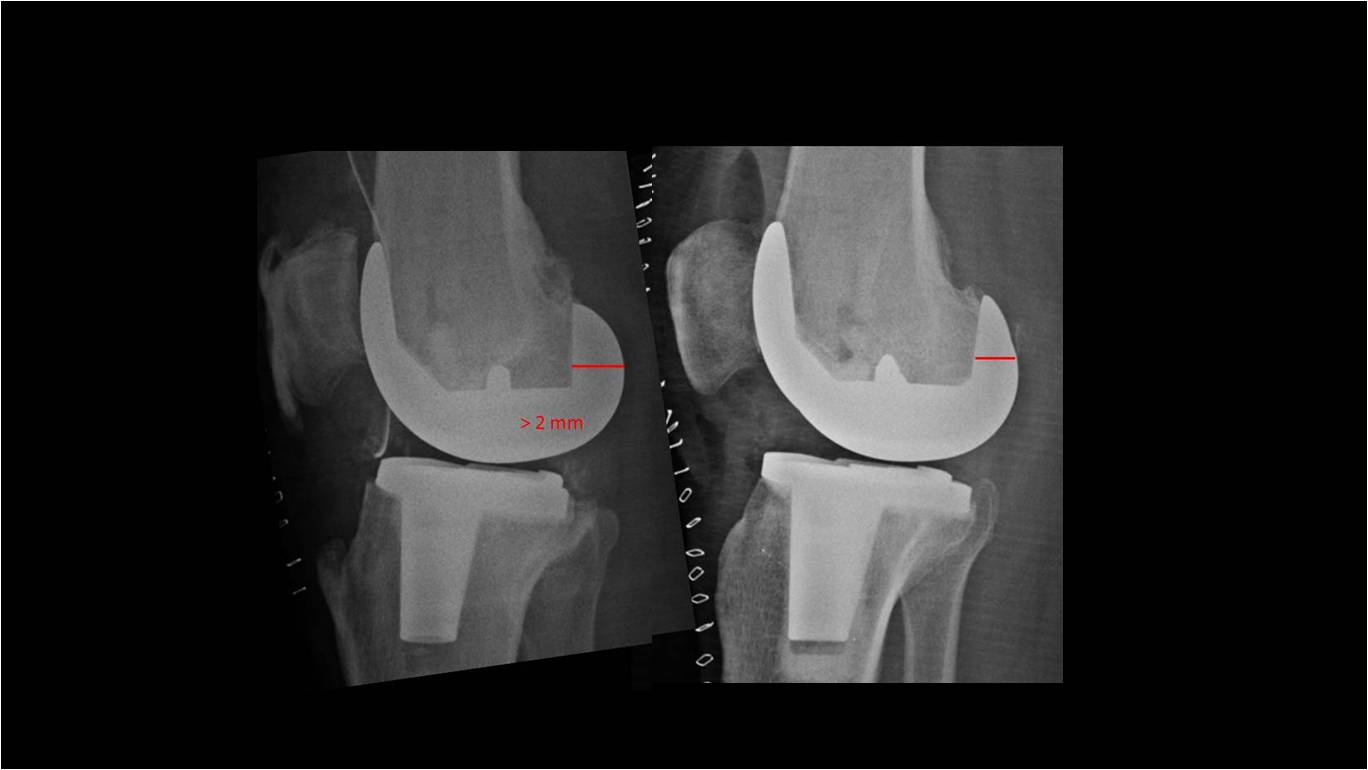

Introducción: El objetivo de este trabajo fue analizar los resultados funcionales y el rango de movimiento entre tres grupos de pacientes con artroplastia total de rodilla: dos utilizando prótesis de alta flexión y el otro con un diseño convencional. Materiales y Métodos: 64 pacientes fueron operados con prótesis total de rodilla Zimmer NexGen®, y 34 pacientes operados con Optetrack ® de alta flexión. Luego de la exclusión de pacientes; 22 pacientes (grupo A) fueron tratados con diseño de alta flexión de Zimmer, 21 pacientes (grupo B) tratados con prótesis Zimmer convencional, y 25 pacientes (Grupo C) con artroplastia Optetrack® PS. La evaluación funcional se realizó con el Knee Society Score, el Western Ontario and McMaster Universities osteoathritis index y la escala analógica visual. Resultados: En el posoperatorio, el promedio de flexión máxima del grupo A subió de 99° a 113º, con un aumento promedio de 14º, en el grupo B de 106° a 118º con una ganancia promedio de 12º y en el grupo C de 110° a 111° siendo la ganancia de 1°. Los resultados funcionales evaluados con KSS y el WOMAC presentaron mejorías en los tres grupos. Conclusión: Las evaluaciones clínicas funcionales son favorables en los tres diseños evaluados. Este estudio muestra que no hay diferencias significativas en la flexión final lograda, y resultados funcionales entre los dos primeros diseños entre sí, si siendo estos significativamente superiores al diseño del tercer grupo luego de un año de seguimiento. Palabras Claves: Prótesis total de rodilla, prótesis de alta flexión, prótesis convencionales, rango de movilidadDescargas